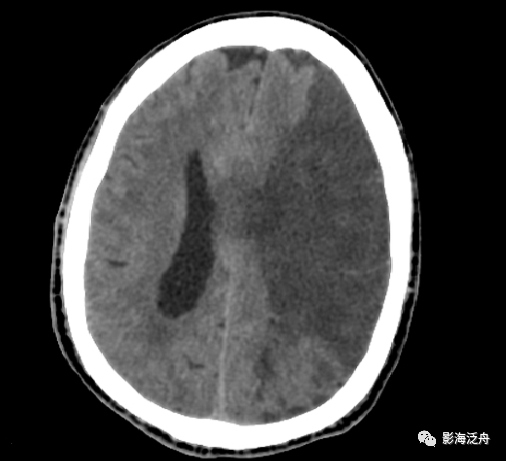

复查ct可见脑室出血逐渐减少,中

脑积水在ct上什么表现?如何区分梗阻性还是交通性?医生讲解